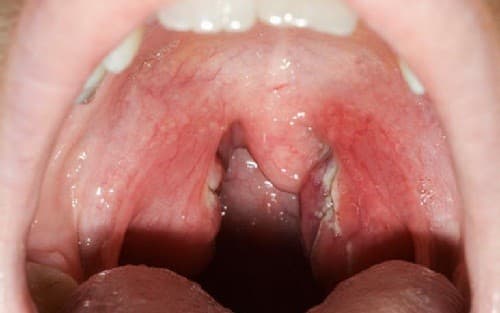

viêm amidan

Dấu hiệu viêm amidan nhiều người không phát hiện sớm bệnh

Do không nắm được những dấu hiệu viêm amidan nên nhiều người không phát hiện sớm bệnh. Nhiều trường hợp cứ nghĩ viêm họng thông thường nên tự dùng thuốc điều trị. Điều này đã gây ảnh hưởng xấu tới sức khỏe và tình trạng bệnh. Trẻ em và trẻ vị thành niên là đối […]

Viêm amidan hốc mủ là gì? gây ra nhiều biến chứng

Viêm amidan hốc mủ là gì? Làm thế nào để phát hiện và điều trị sớm bệnh…là câu hỏi được nhiều người đặt ra.  Viêm amidan hốc mủ nếu không được phát hiện và điều trị sớm sẽ gây ra nhiều biến chứng nguy hiểm. Amidan nằm ở vị trí cầu nối giữa đường thở […]

Triệu chứng viêm amidan hốc mủ

Khi bạn bị đau họng, ho, sốt hoặc thấy có mủ quanh amidan thì có thể đó là những triệu chứng viêm amidan hốc mủ. Nhiều người do thiếu kiến thức về căn bệnh này nên không phát hiện sớm. Viêm amidan hốc mủ nếu không được điều trị kịp thời có thể gây biến […]